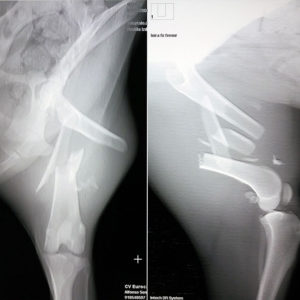

LOIRA llegó a la perrera con el fémur fracturado. Sus anteriores propietarios, por ser educados y llamar de alguna forma a estas «personas» la tiraron por la ventana un buen día …. fue un milagro que la perra sobreviviera tan solo con una pata destrozada.

Loira ha necesitado tres cirugías para reconstruir el hueso de su extremidad posterior y muuuchos meses de rehabilitación para ser capaz de andar de nuevo a 4 patas.